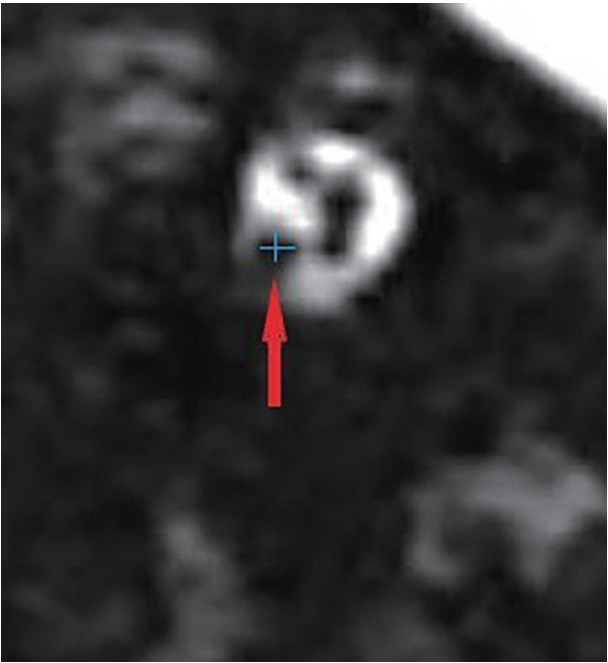

Abstract Image